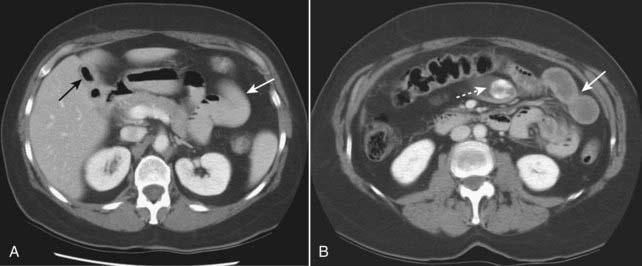

Figure 15-14 Necrosis of bowel from mesenteric ischemia.

Axial CT image of the pelvis demonstrates multiple loops of bowel with punctate collections of air throughout their walls consistent with pneumatosis (solid white arrows). The patient had widespread ischemia of bowel from mesenteric vascular disease. Pneumatosis that results from bowel necrosis is an ominous sign.

Figure 15-13 Pneumatosis cystoides intestinalis.

Axial CT scan of the upper abdomen windowed for lung technique shows a cluster of air-containing cysts (solid white arrows) associated with the left colon, characteristic of pneumatosis cystoides intestinalis, a rare but benign condition in which air-containing cysts form in the submucosa or serosa of the bowel.